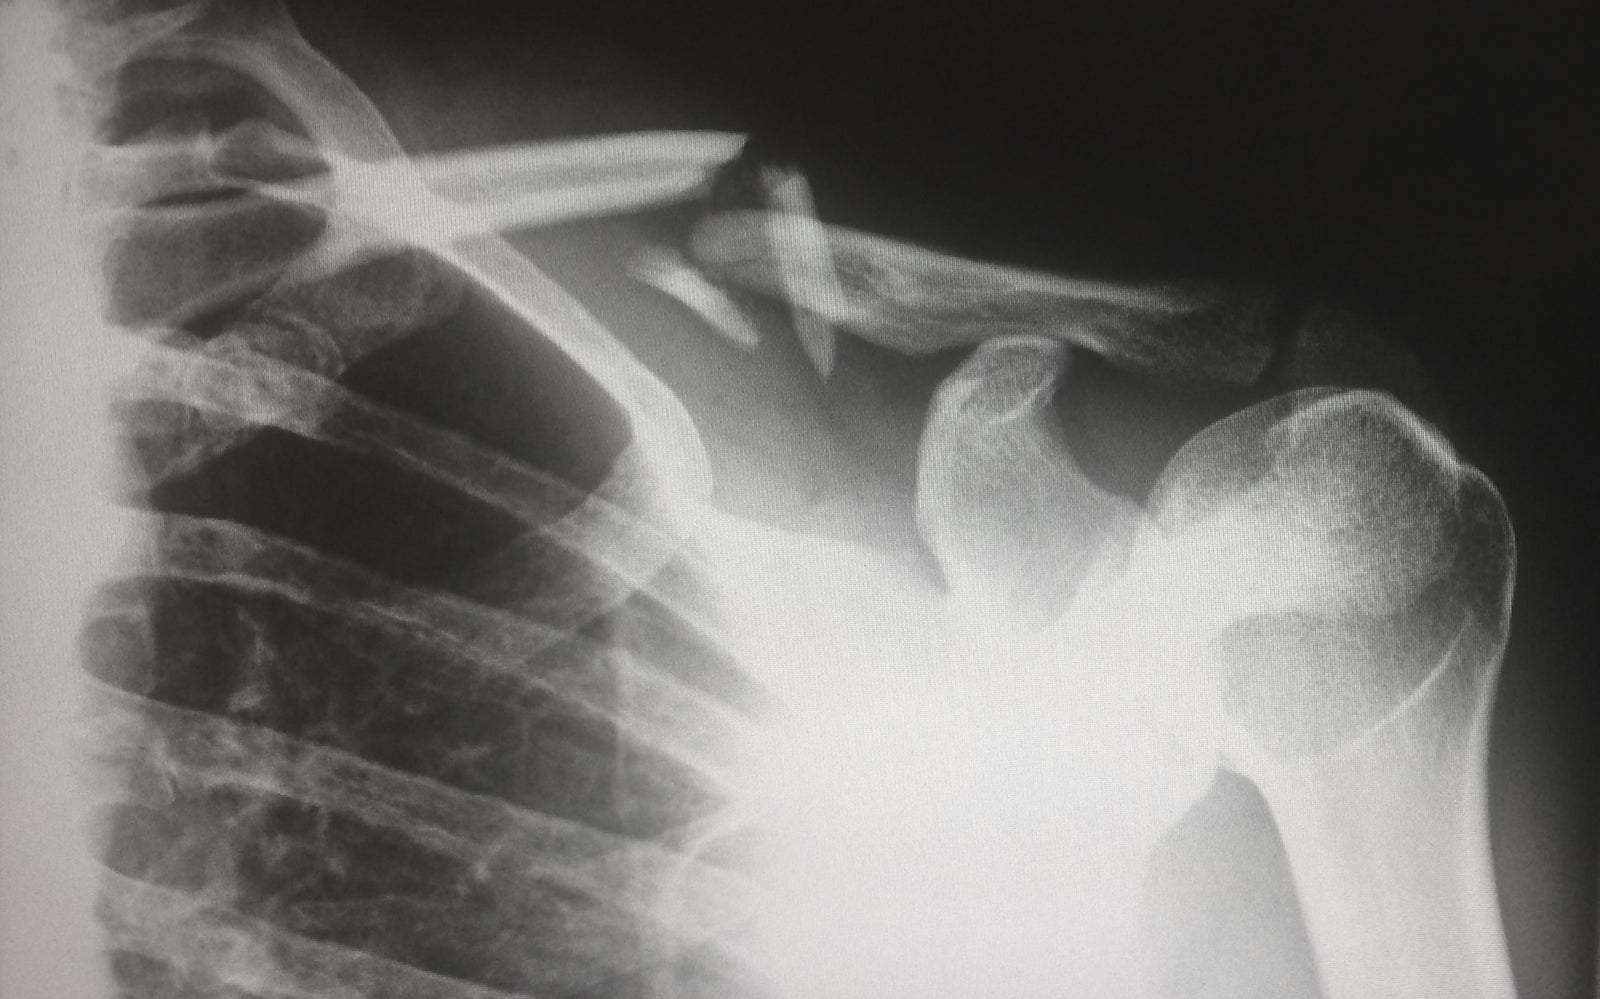

The plaintiff/patient attended an urgent care facility for treatment following an injury to her wrist. Dr. P ordered an x-ray. His diagnosis was a “possible” hairline fracture of her scaphoid bone. The patient was discharged with the advice that she rest, use ice and do her best to immobilize and compress the wrist. The subsequent report of the radiologist suggested the possibility of the fracture again and recommended a follow-up x-ray. On the radiological report was some writing which read “dx scaphoid #” and “N/A”. The patient did not receive any follow-up. Her pain worsened and her family doctor referred her to an orthopedic surgeon who performed two surgeries. She felt the delay had resulted in further surgeries and care for an injury that would not have occurred but for the urgent care staff's failure to follow up with her.